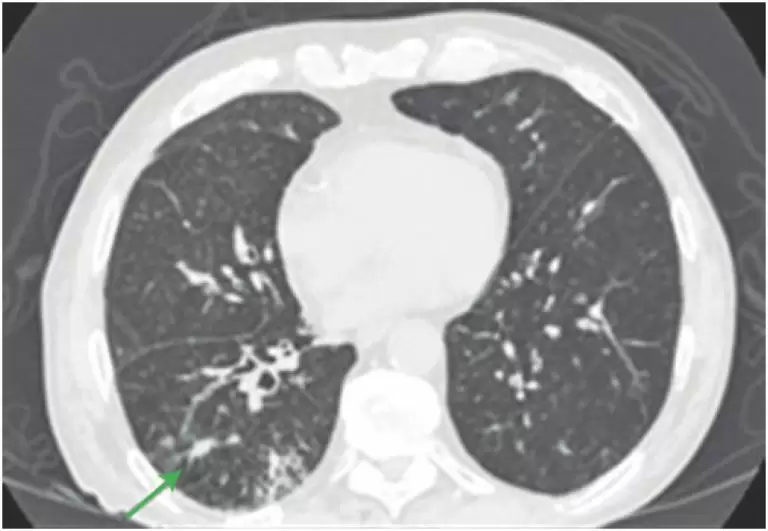

ABSTRACT The X-linked spinal and bulbar muscular atrophy (Kennedy’s disease) is a rare X-linked, recessive, lower motor neuron disease, characterized by weakness, atrophy, and fasciculations of the appendicular and bulbar muscle. The disease is caused by an expansion of the CAG repetition in the androgen receptor gene. Patients with Kennedy’s disease have more than 39 CAG repetitions. We report a case of 57-year-old man, resident of Monte Dourado (PA, Brazil) who complained of brachiocrural paresis evolving for 3 years along […]